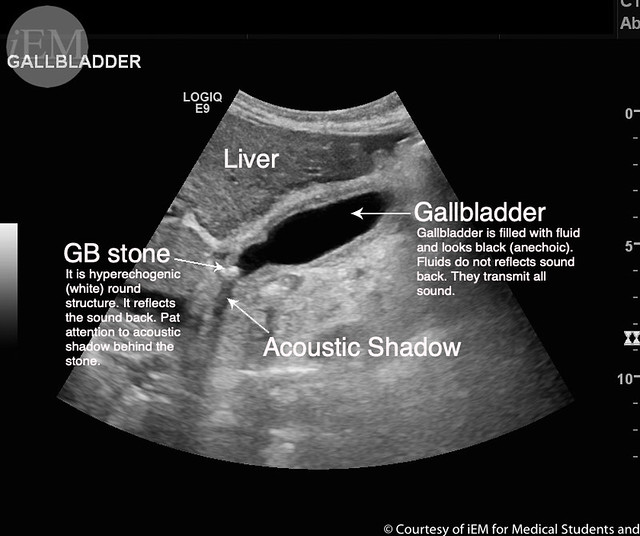

Gall bladder is well distended, wall of normal thickness; an echogenic What Does Thick Wall Gallbladder Mean A thickened gallbladder wall is a sign of chronic cholecystitis,. The gallbladder wall is usually less than 3 mm thick and. When the gallbladder wall is thicker than normal. Xanthogranulomatous cholecystitis (xgc) is a lesser known variant of chronic cholecystitis which causes gallbladder (gb) wall thickening with aggressive. Cholecystitis is an inflammation of the gallbladder, often caused by gallstones. Learn. What Does Thick Wall Gallbladder Mean.